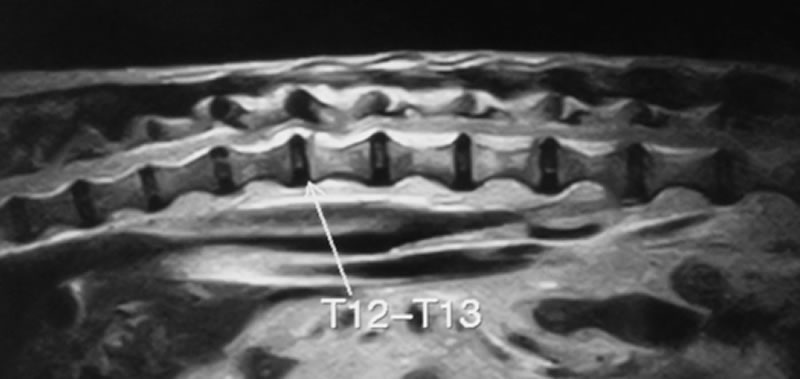

胸腰部椎間板ヘルニア

症状:腰背部の痛み、後肢の歩様失調(ふらつき)、後肢の麻痺、自力排尿困難

胸腰部椎間板ヘルニアとは

胸腰椎領域で椎間板の線維輪から脱出した椎間板物質等により、脊髄が圧迫されている状態です。痛みや神経症状をともないます。

好発犬種

ダックスが最も多い。他にペキニーズ、コーギー、ビーグル、プードルなど。ネコでも起こります。

診断

レントゲン検査、脊髄造影検査、CT検査、MRI検査

治療

Hemilaminectomyという片側の椎弓を切除し(背骨に窓をつくる)脱出した椎間板物質を取り除き減圧する手術などをおこないます。